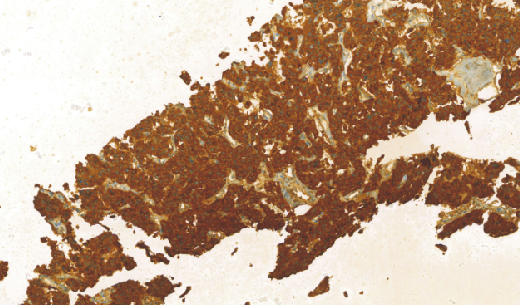

Calcitonin(CT)兔抗人降钙素多克隆抗体

- 阳性部位:胞质

- 适用组织:石蜡切片/冰冻切片

- 预处理:热修复